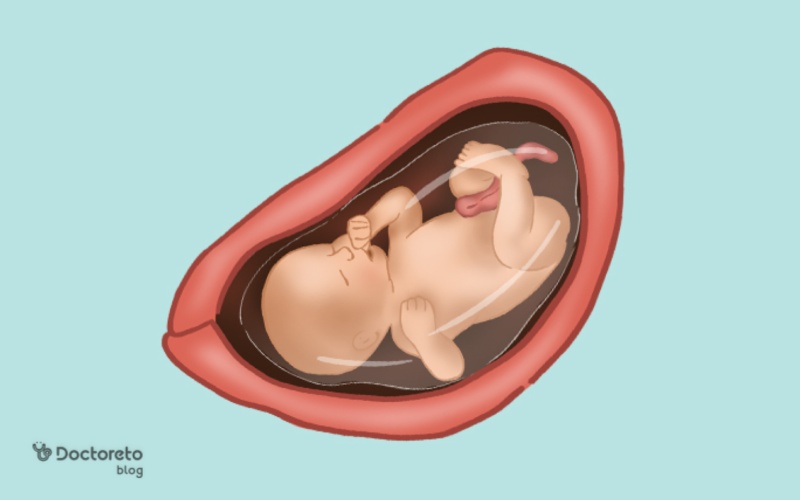

عکس جنین در هفته 32 بارداری

عکس جنین در هفته 32 بارداری جنین را در حالت خمیده نشان میدهد، با سر به سمت پایین و دست و پا نزدیک بدن. در این حالت، شکل کلی بدن، سر، دستها و پاها واضح و قابل تشخیص است و حرکات کششی و لگدهای او بهصورت سادهسازیشده دیده میشود. همچنین، جنین سی و دو هفته در این تصاویر تقریباً اندازه نهایی خود را یافته و حالت جمعشده داخل رحم را نشان میدهد.